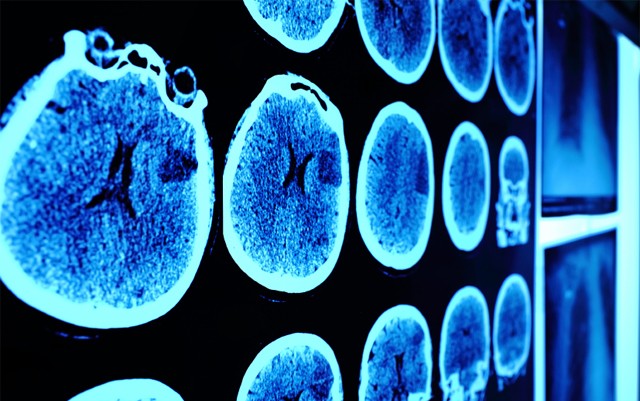

Duke University is responsible for this historically game and mind changing study. Researchers at Duke headed the best possible scenario in this study: analyzing the cognitive ability, habits, successes and failures of identical twins. Twins give this study its advantage above others because they come from the same background, upbringing and have almost the exact same body chemistry. These factors weed out much of the uncertainty in comparison to tests done on people with very different make-ups and backgrounds.

“The data collected from the identical twins fails to support the implication that marijuana exposure in adolescence causes neurocognitive decline,” according to the study.

The numbers gathered from the twin study suggest that teenagers who experience “intellectual stagnation” are the ones who are most likely to develop heavy cannabis use habits later on in life. This is mainly due to the boredom factor, where high IQ students end up tuning out because they lack interest in school studies that are geared to their lower intelligence peers, depriving them of essential intellectual challenge and cognitive stimulation. According to the study, these types of teens are “predisposed to intellectual stagnation in middle school and are on a trajectory for future marijuana use.”